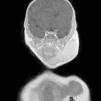

Neonato de 24 días de vida que presenta un aumento de volumen en la hemicara izquierda, de consistencia firme, sin alteraciones inflamatorias ni cambios de coloración de piel suprayacente; no presentaba dolor a la palpación. Ante el buen estado general del paciente, analítica con amilasemia normal y ausencia de reactantes de fase aguda se inició tratamiento antibiótico a la espera de hemocultivo, serología vírica y controles ecográficos (fig. 1). No se solicitó ecografía inicial por borrar ángulo mandibular y pensar en parotiditis infecciosa como primer diagnóstico diferencial. Una semana después, con hemocultivo y serología negativos se realizó ecografía Doppler, que mostró cambios inflamatorios con importante vascularización en parótida izquierda, de tamaño elevado (4cm). Se sospechó entonces de hemangioma infantil como causa más probable, realizándose resonancia magnética (RM) craneal y de cuello, donde se objetivó hiperseñal en secuencias T2, hiposeñal en T1 y significativa captación temprana tras contraste, en región parotídea izquierda incluyendo zona submandibular hasta línea media (figs. 2 y 3). Con diagnóstico de hemangioma infantil parotídeo (focal vs. integrante de hemangioma en región V3), y descartándose síndrome PHACE y extensión a vía aérea se inició tratamiento oral con propranolol al mes y medio de vida, con aumento progresivo hasta 3mg/kg/día, con buena tolerancia. En controles posteriores en consultas (a los 2 meses y medio), la masa era ya imperceptible.